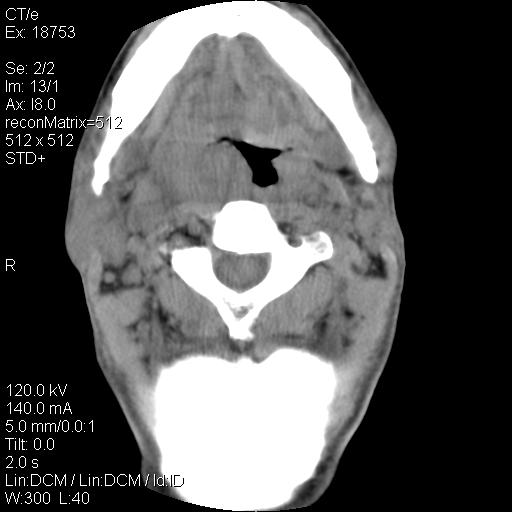

标题: CT21693:男 58岁 右侧咽部疼她2天余 PE:右侧扁桃体肿大 压痛 [打印本页]

标题: CT21693:男 58岁 右侧咽部疼她2天余 PE:右侧扁桃体肿大 压痛

右化脓性扁桃体炎症伴咽后壁脓肿形成.

以下是引用zjzjr在2009-8-19 21:07:00的发言:[br]右化脓性扁桃体炎症伴咽后壁脓肿形成.